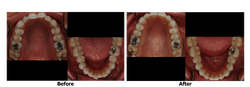

Invisalign wearers utilize a graduated series of clear and removable aligners to shift teeth into straighter alignment over time. These thin plastic aligners are so clear that most people don't even notice them when you speak or smile. The aligners are custom fit for each patient and worn for two weeks and are then disposed of and a new set is worn until the sequence is completed and successful results are achieved. This graduated process gently shifts teeth into place.

Unlike traditional braces which are affixed to teeth, aligners are easily removed for hygiene and during meals. While the aligners are completely removable, for ideal results aligners must be worn 20-22 hours a day. Clear aligners may be used alone or as part of a comprehensive plan to help patients achieve the level of cosmetics and/or health that they desire.